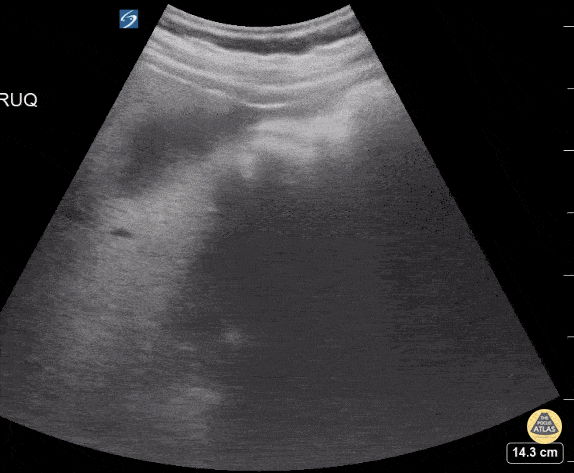

17 yo M with epigastric and right upper quadrant pain. Unable to tolreate PO. POCUS shows a thickened gallbladder wall with cholelithiasis consistentw tih cholecystitis. Contributor: Kathryn Pade, MD, Rady Children's Hospital San Diego